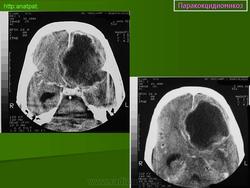

ГМ. Паракокцидиомикоз. +

Паракокцидиомикоз.

Множественные "узловые образования" имитирующие метастазы.